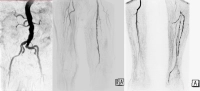

Exemplo de filme

PM 324-1

Zum Vergrößern bitte anklicken

• estenoses subtotais da artéria femoral superficial esquerda

• oclusão dos segmentos I – III da artéria poplítea

• oclusões parciais de todas as artérias da perna inferior

• oclusão dos arcos primário e secundário do pé

Status pós-bypass venoso femoro-poplíteo à direita, veia safena magna autóloga esgotada, calibre esquerdo muito pequeno → bypass aloplástico.